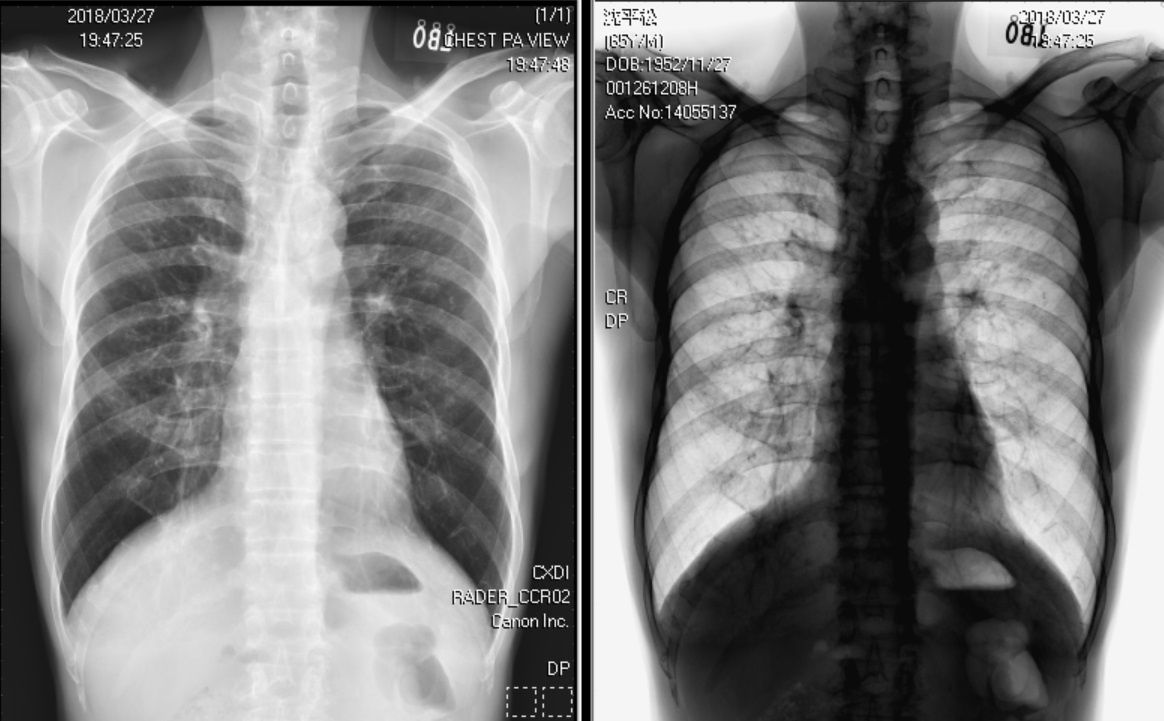

Figure 1. CXR image at OPD:

Normal chest X-ray and inverted chest X-ray.